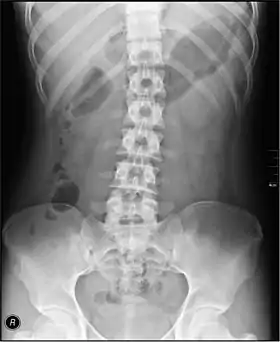

Projections

The standard abdominal X-ray protocol is usually a single anteroposterior projection in supine position.[3] Special projections include a PA prone, lateral decubitus, upright AP, and lateral cross-table (with the patient supine). A minimal acute obstructive series (for the purpose of ruling out small bowel obstruction) includes two views: typically, a supine view and an upright view (which are sufficient to detect air-fluid levels), although a lateral decubitus could be substituted for the upright.

Coverage on the x-ray should include from the top of the Liver (or diaphragm) to the pubic symphysis. The abdominal organs included on the xray are the liver, spleen, stomach, intestines, pancreas, kidneys, and bladder.